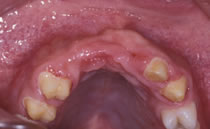

ブリッジを除去し感染した歯を抜歯した後の状態です。

歯槽骨は水平的、垂直的に大きく欠損してしまい正常な形の歯を入れることができません。またこの状況が談笑時に見えてしまいます。 |